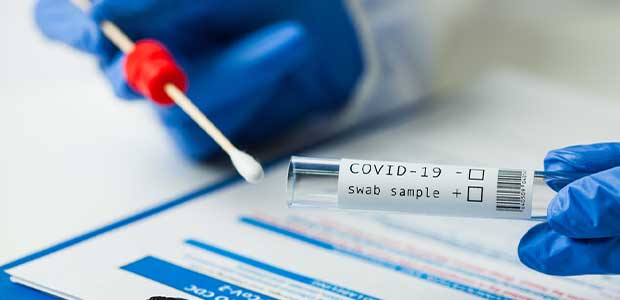

Listen in on top safety news topics such as OSHA's new National Emphasis Program, the FDA's recommendations for coronavirus screening tests and how to thoughtfully encourage COVID-19 vaccinations without mandates.

Health experts say it’s important to get tested even if you’re asymptomatic.